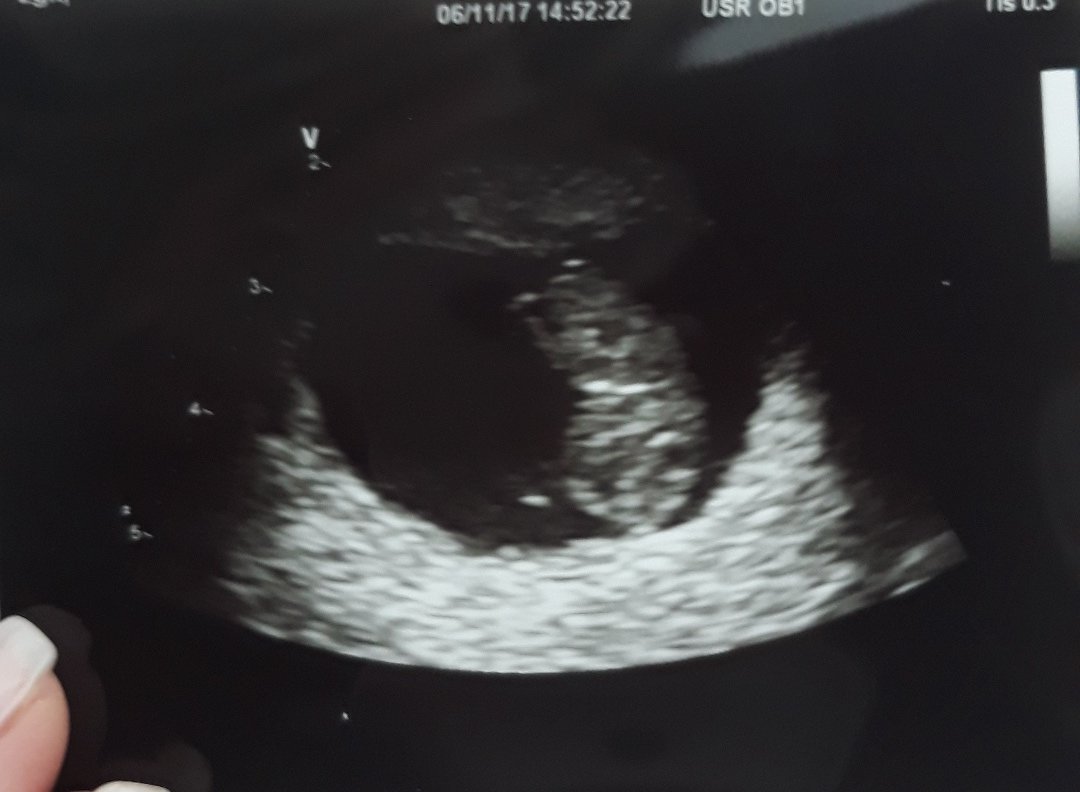

Całe 20 mm, a 2 tygodnie temu były 4 mmCo do obecnosci przyszlego tatusia to powiem Wam ze dla mojego od poczatku bylo takie oczywiste ze idzie zeo mna juz na pierwsza wizyte ze nie chcial nawet slyszec zeby poczekal na korytarzuteraz ciesze sie ze bylismy wtedy razem i pierwsze bicie serduszka uslyszelismy wlasnie razem

wczoraj już nie miałam siły pisać, wczoraj rano pod prysznicem było mi tak słabo że zwymiotowałam, nie wiem czy to zapach jakiegoś kosmetyku czy co...potem wizyta u gina. Siedziałam od 11-15!!! Masakra, takie opóźnienia że dramat. Ale byłam i wszystko ok. Dziubuś ma 20 mm i bije piękne serduszko, dostałam milion badań do zrobienia min. usg piersi, HIV itd.